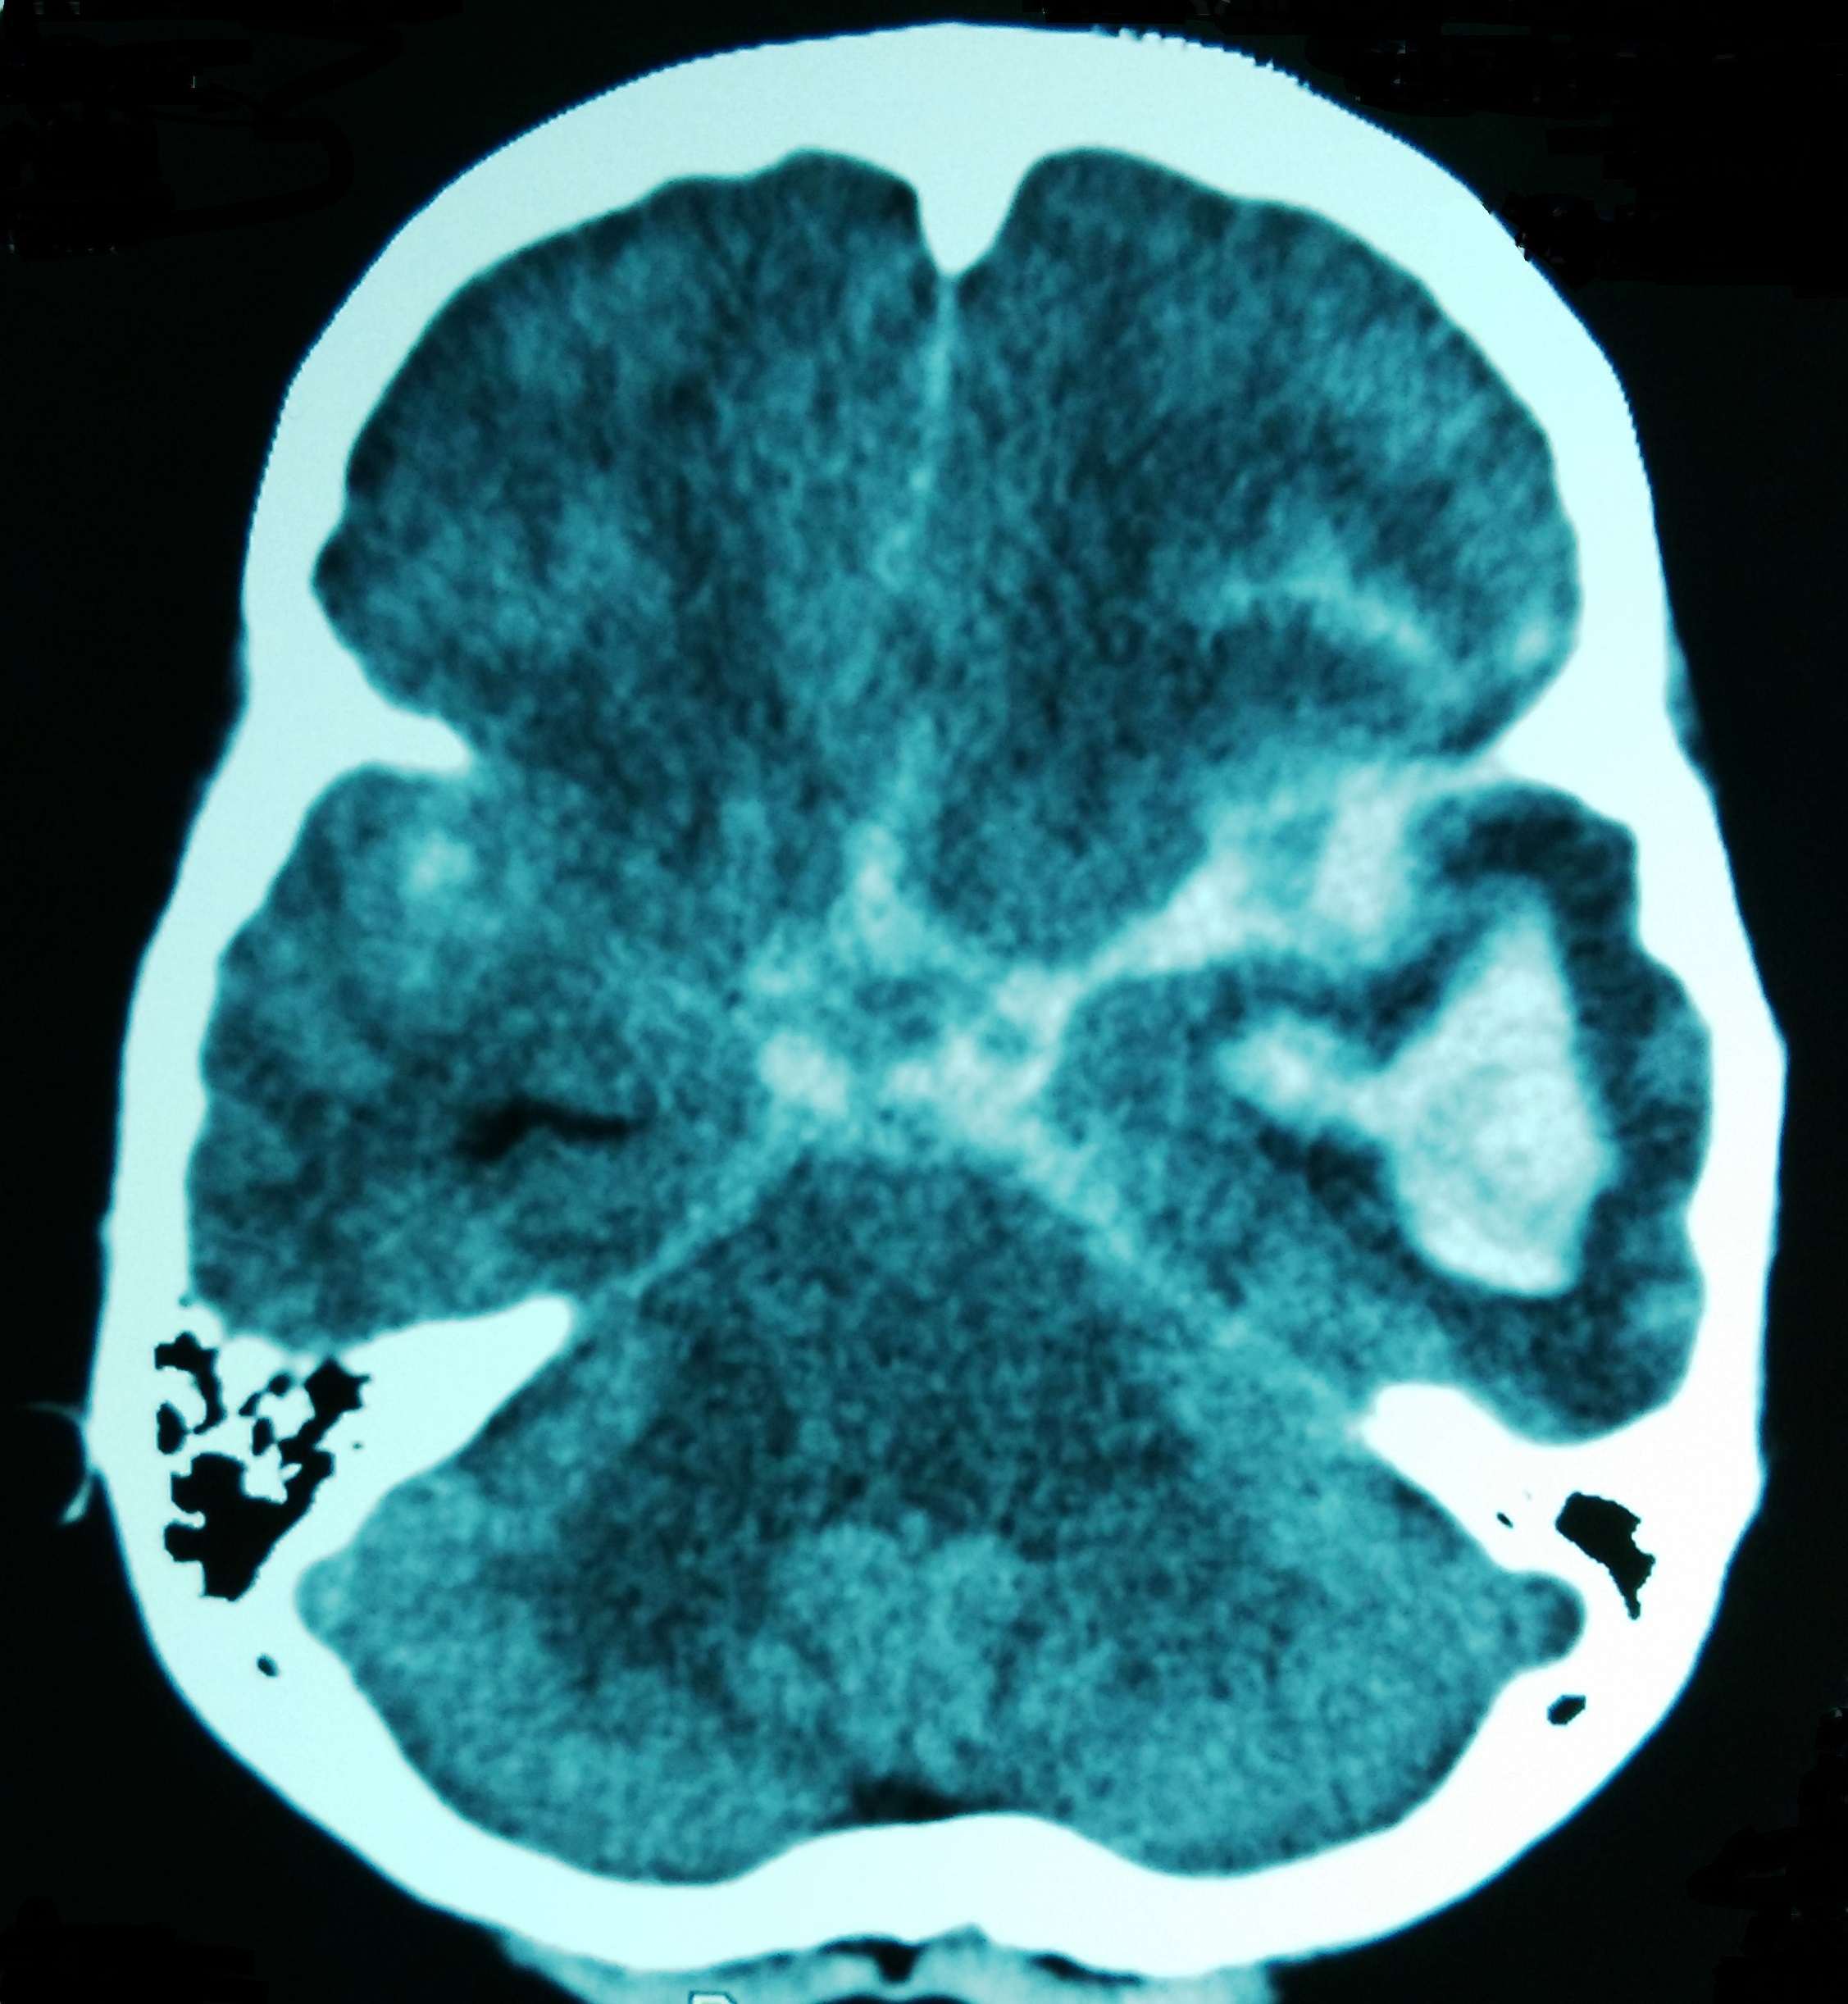

В поставяне на диагнозата главна роля заема лумбалната пункция – при негативни резултати от невроизобразителните методи (компютърна томография и ядрено-магнитен резонанс) нейното приложение е задължително.

Изследването на ликвор може да спомогне и за отдиференциране на диагнозата менингит, която дава сходни симптоми. Образната диагностика също е подходящ избор в диагностично-диференциален план. При болните в по-млада възраст е наложително да се направи мозъчна панангиография и то още в първите 24-48 часа от възникване на заболяването. Чрез това изследване може да се установят мозъчно-съдови малформации и дефекти (като споменатата аневризма), които се лекуват спешно по оперативен път.